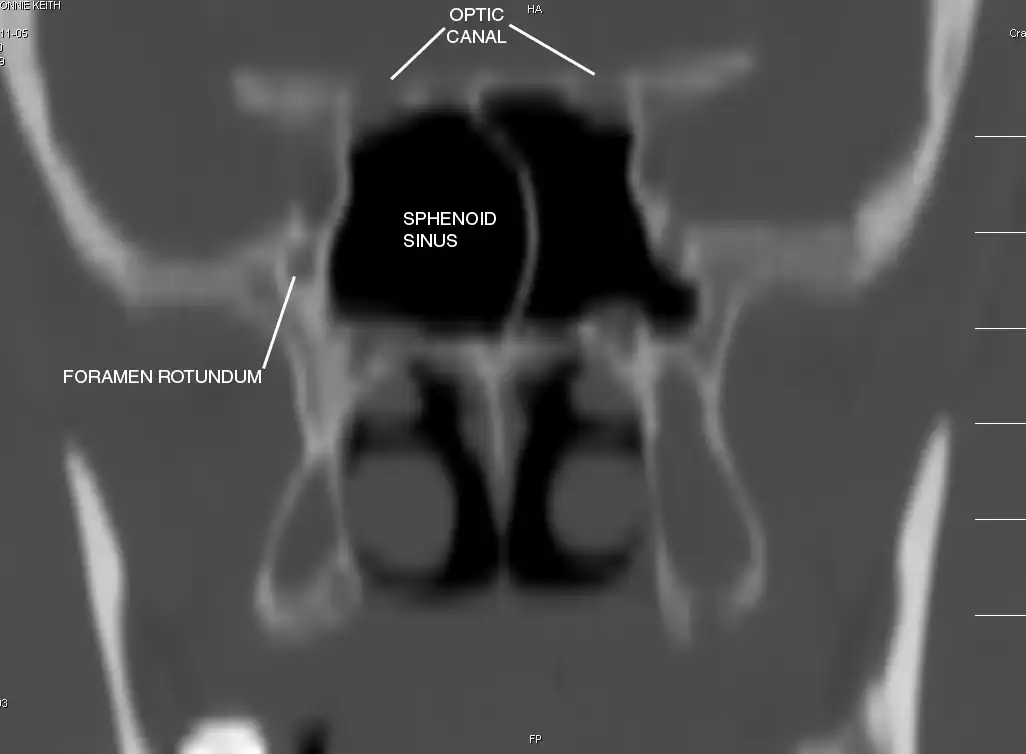

Sphenoid Sinus has 12 close structures: II, III, IV, V1, V2, VI, Vidian Nerve, Carotid artery, Brain, Dura, Pituitary.

- II = Optic Nerve: 25-50% with bony dehiscence into sphenoid sinus.

- V2 = Maxillary division, Trigeminal Nerve: exits foramen rotundum, superomedial to V3's foramen ovale.

- C = Carotid Artery: often with bony dehiscence into sphenoid. Together with CN II forms opticocarotid recess.